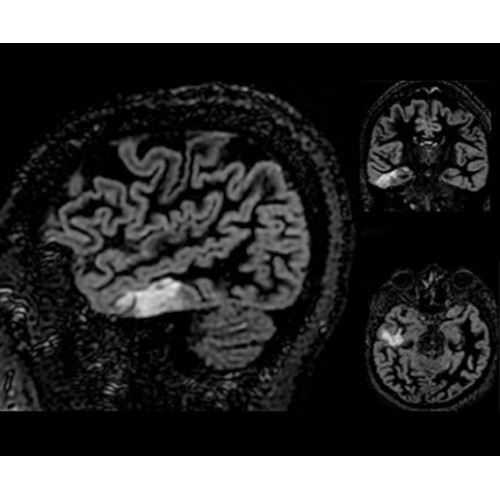

• NeuroWorks — универсальное решение для визуализации анатомии головного мозга, позвоночника, сосудов и периферических нервов с четкой дифференциацией тканей.

• ImageWorks — повысит производительность МРТ благодаря визуализации высокого качества с MAGIC, четкими результатами пост-процессинга с READYView.